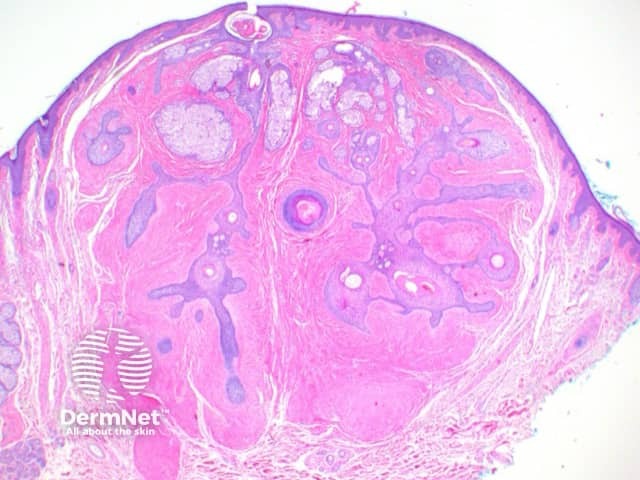

Scanning view shows dilated follicular structure or structures, with radiating mature sebaceous lobules (figures 1, 2). Surrounding the distorted hair follicles there may be thin anastomosing epithelial strands (figure 3). The stroma surrounding the epithelial units is frequently composed of dense collagenous tissue (figure 1-3) and can show prominent clefting to the surrounding adjacent uninvolved dermis (figure 1). Additional stromal changes can include increased vascularity or pockets of adipocytes consistent with increased stromal fat (figure 4).

Figure 1